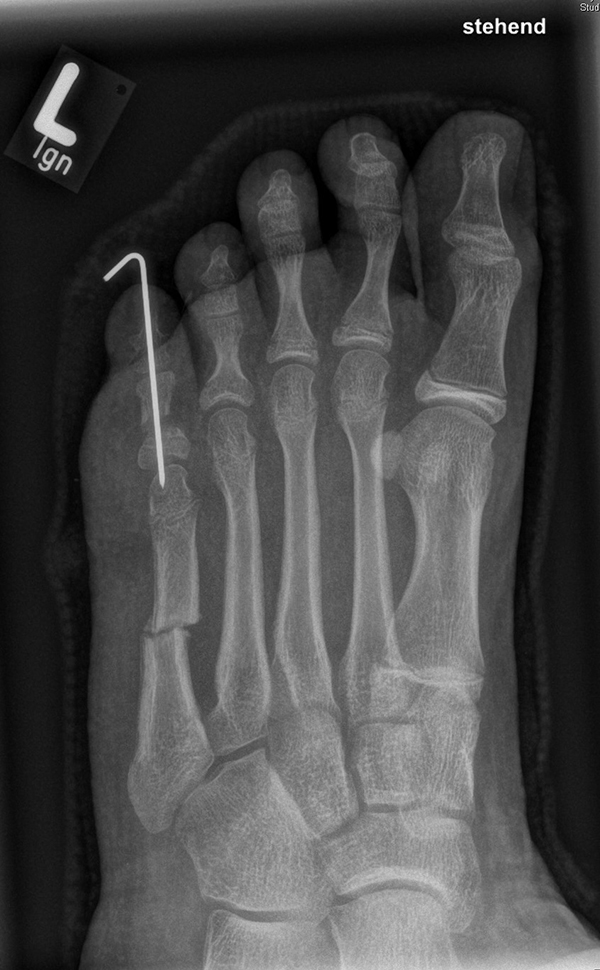

In der Regel bestehen aktive Wachstumsfugen bei Mädchen bis zum 12. und bei Jungen bis zum 14. Lebensjahr, mit Abweichungen von einem Jahr nach unten und nach oben. Präzise Informationen unter anderem darüber gibt das präoperative Röntgenbild (Abb. 2).

Abb. 2 a-c: offene Wachstumsfugen MT I Basis und Zehen (a), teilweise geöffnete Wachstumsfugen (b) und geschlossene Wachstumsfugen (c).

Zum Lesen der Bildbeschreibung und zur Vollansicht bitte die Bilder anklicken. Bilder: A. Helmers.